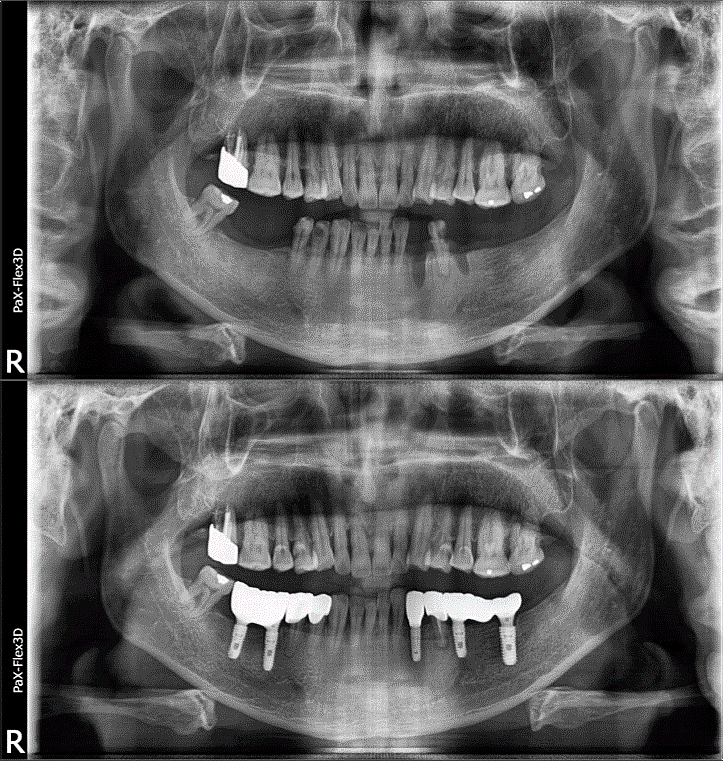

68세 남성

(전) 2021-11-05, (후) 2022-08-26

임플란트/크라운 시술 후

음식 섭취뿐만 아니라, 심미적인 개선으로

삶의 질이 높아진 환자분의 사례

치과에서 어떤 치료와 관리를 받는지에 따라 남은 삶의 질이 크게 달라질 수 있음을 절실히 느끼며